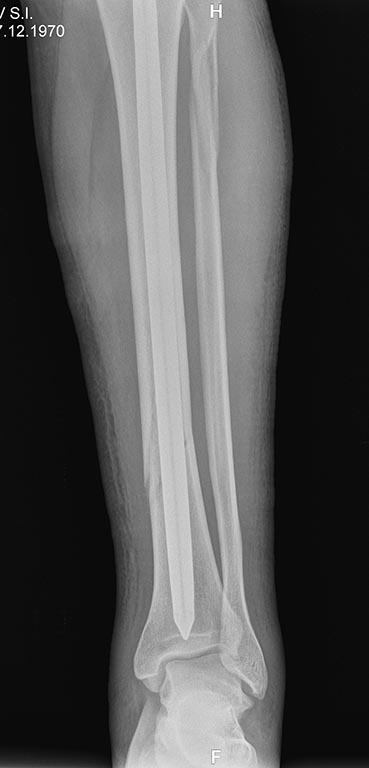

Уважаемые коллеги, по просьбе официального представителя компании FIXION

в Украине -представляем вашему вниманию клинический случай перелома 42

A1 (для нас этот случай вызвал интерес в связи с достаточно низким

расположением линии перелома большеберцовой кости и

отсутствием у нас опыта применения FIXION).

Пациент 1970г.р., соматически здоров.

Непрямой механизм травмы, низкая энергия. Операция на 7е сутки.

Интраоперационно использовали дистрактор.

Возникали сомнения в достижении стабильной фиксации

дистального фрагмента без блокировки винтами. Итог - синтез стабильный,

дозированная нагрузка с первого дня. Результаты представлены на

рентгенограммах.